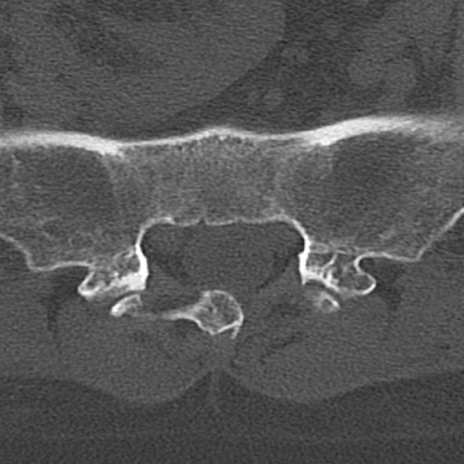

腰椎CT

冠状断像